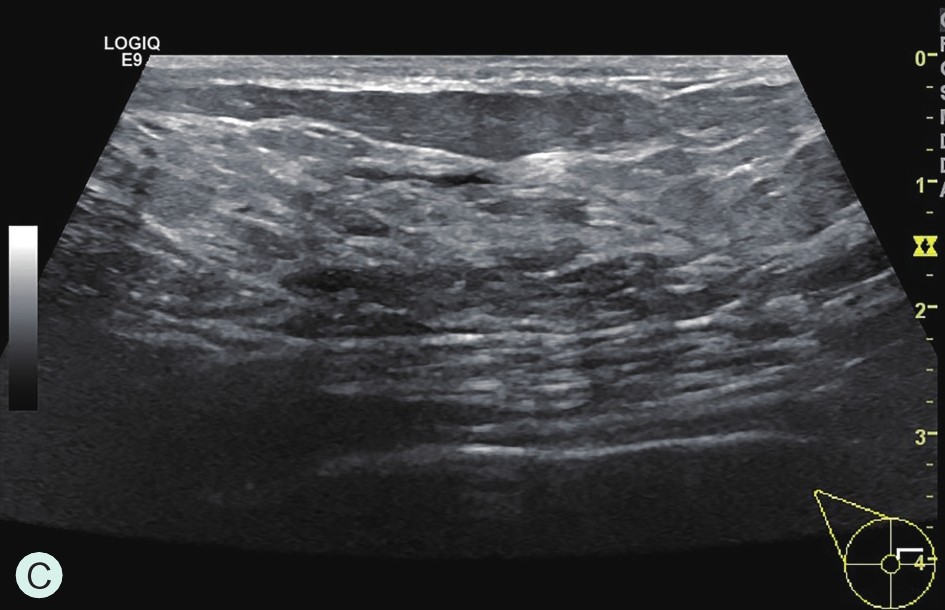

A级:几乎完全为脂肪型(图1-3-1A、图1-3-2A、图1-3-3A)。

图1-3-1 乳腺X线不同乳腺密度

A.脂肪型;B.散在致密型;C.不均匀致密型;D.极度致密型

B级:散在纤维腺体致密型(图1-3-1B、图1-3-2B、图1-3-3B)。

C级:不均匀致密型(可能掩盖小肿块)(图1-3-1C、图1-3-2C、图1-3-3C)。

D级:极度致密型(降低乳腺钼靶摄影的敏感性)(图1-3-1D、图1-3-2D、图1-3-3D)。

图1-3-2 乳腺超声不同乳腺密度